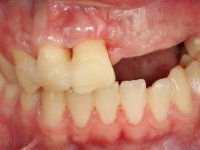

Paciente do sexo masculino, com 22 anos de idade e não fumador. Apresentou-se na consulta 6 meses após um acidente de viação em que perdeu os dentes 21, 22, 23 e 24. Os dentes 12 e 11 apresentavam mobilidade grau 3 apresentando-se também com extracção indicada. A arquitectura gengival da zona desdentada apresentava-se retraída e planificada.

Foi aconselhada a extracção dos dentes 12 e 11 e esperar mais 3 meses para se conseguir uma completa cicatrização da zona. Estabilizada a situação fazer-se –ia um enceramento de diagnóstico que dando origem a uma guia imagiológica permitiria fazer uma TAC. em que o posicionamento idealizado dos dentes pudesse ser relacionado com o património ósseo. O objectivo seria fazer uma ponte cerâmica implanto suportada.